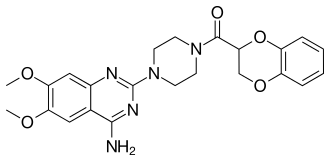

| Doxazosin | Cardura

Cardura XL |

|

Competitive blocking of α1 receptor.[10] | Lowers blood pressure.[2] |

|

|